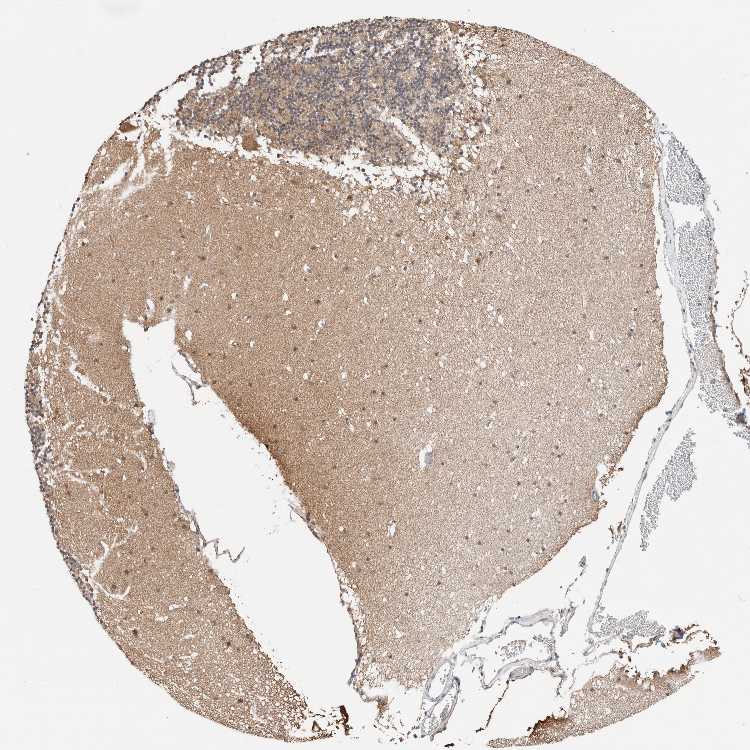

TISSUE PRIMARY DATA CEREBELLUM Show tissue menu

CEREBELLUM - Antibody stainingi

Antibody staining in the annotated cell types in the current human tissue is reported as not detected, low, medium, or high, based on conventional immunohistochemistry profiling in selected tissues. This score is based on the combination of the staining intensity and fraction of stained cells.

Each image is clickable and will lead to virtual microscopy that enables deeper exploration of all samples and also displays staining intensity scores, fraction scores and subcellular localization as well as patient and tissue information for each sample.

Antibody HPA030419Antibody HPA030420Antibody HPA030422Antibody CAB025196Antibody CAB080286Antibody CAB080287

Purkinje cells LowNot detectedHighMediumNot detectedHigh

Cells in granular layer Not detectedNot detectedMediumMediumNot detectedNot detected

Cells in molecular layer Not detectedNot detectedMediumMediumNot detectedNot detected